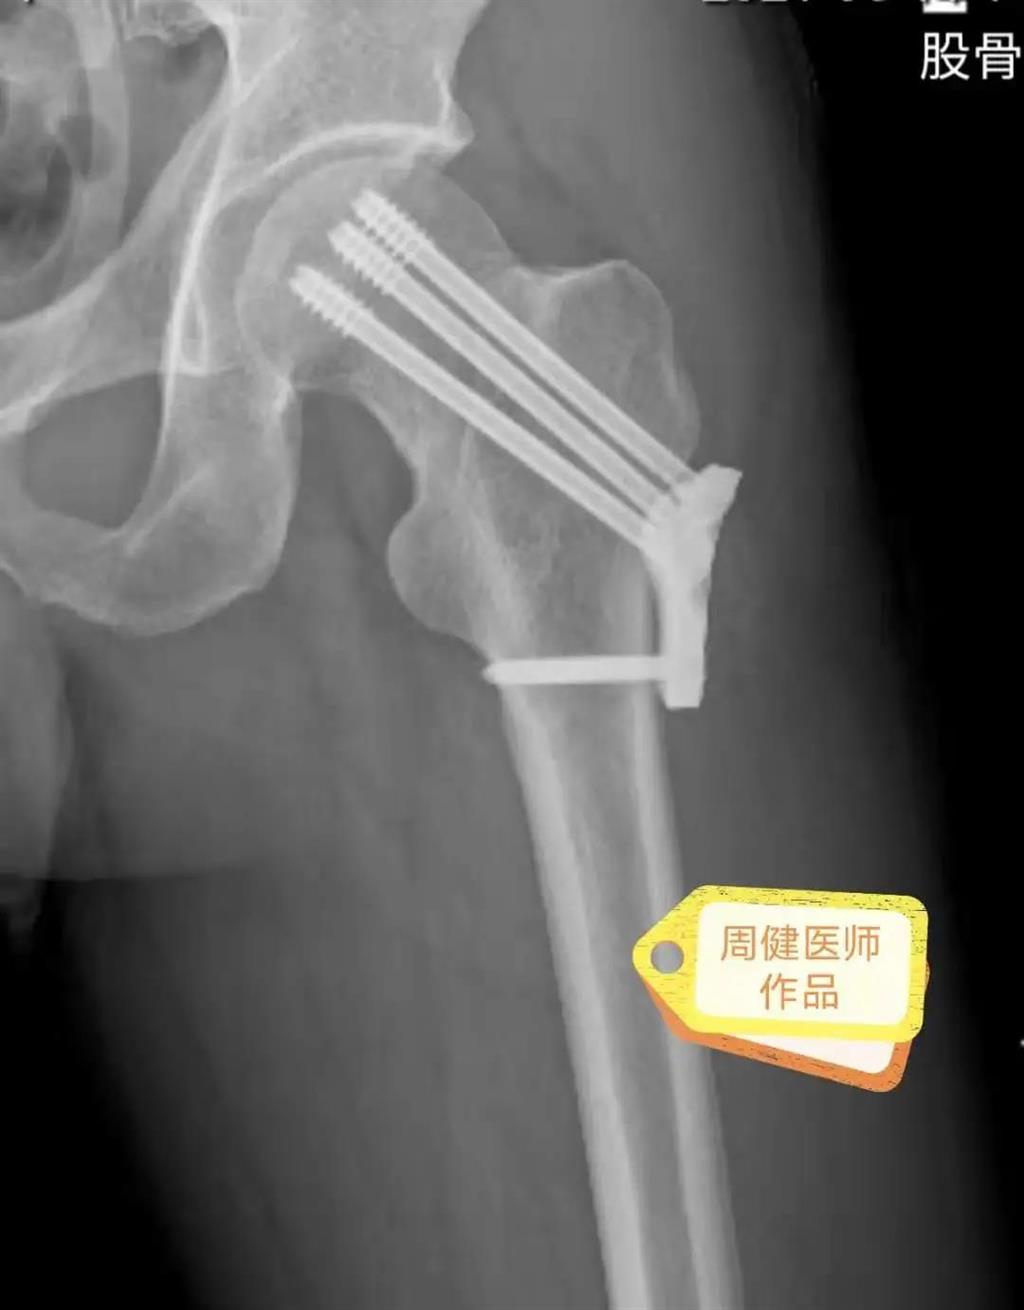

6月30日的“關節(jié)置換術”,患者是一位上了年紀的老人,苦于病痛折磨多年的他四處“求醫(yī)問藥”,最后在多位專家醫(yī)師及病友地力薦下選擇了和平國際醫(yī)院,在醫(yī)師團隊“偷天換日”般的手術后,老人成功告別了苦纏多年的病痛。

周健說,這場“關節(jié)置換術”對于他們團隊而言其實算是比較普通的手術,因為做過很多同類的手術,成功案例繁多,因此在手術操作上有較多地實操經驗。“不過話雖如此,作為醫(yī)生我們對于每一場手術都會全力以赴,這是為醫(yī)者的職責也是義務。”